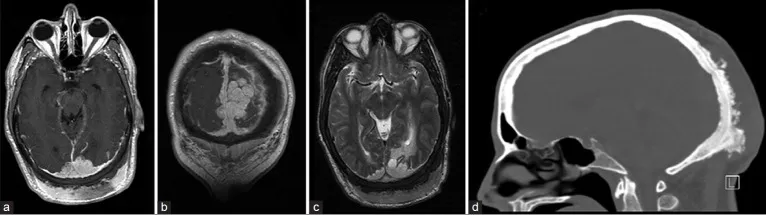

一名48岁男性因持续3天加重的头痛和视物模糊至急诊就诊。体格检查发现存在下方视野偏盲,枕后部可触及巨大坚硬隆起,表面皮肤无异常。患者无吸烟史,无恶性肿瘤病史,胸部、腹部及骨盆的筛查性计算机断层扫描(CT)未提示恶性病变。头颅磁共振成像及磁共振血管成像(MRI/MRA)显示一个11×5cm的肿块,跨越幕上及幕下延伸至双侧顶叶与枕叶,并侵犯上矢状窦、窦汇及横窦近端(图1)。

图1.轴位(a)与冠状位(b)增强T1加权MRI显示肿瘤包绕上矢状窦后部并延伸至窦汇。可见枕部头皮异常增厚。(c)轴位T2加权MRI序列显示枕叶白质异常高信号,符合肿瘤实质侵犯所致血管源性水肿。(d)增强CT扫描骨窗位矢状面图像显示肿瘤浸润导致枕骨同时存在骨质增生和增厚